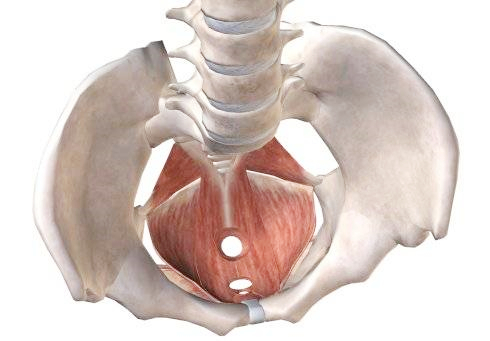

- 骨盆是人体的重要结构之一,承受着上半身的重量,又控制着下半身的动作。有几十条肌肉组织相连。对调节身体姿势起着重要作用。而与骨盆密切相关的盆底肌与身体的健康息息相关。很多人都不太知道盆底肌用力是什么感觉。关于盆底肌,经常听到的引导方式有:① 想像一个手帕,从中心点被往上拉起来的感觉 ② 想像就像一个帐.....

- 盆底解剖结构,女性盆底是由封闭骨盆出口的多层肌肉和筋膜构成,有尿道、阴道和直肠贯穿其中。盆底肌肉群、筋膜、韧带及其神经构成了复杂的盆底支持系统,其互相作用和支持,承托并保持子宫、膀胱和直肠等脏器在盆腔的正常位置。若盆底结构和功能发生异常,可影响盆腔脏器位置及功能,甚至引起分娩障碍,而分娩处理不当,亦.....